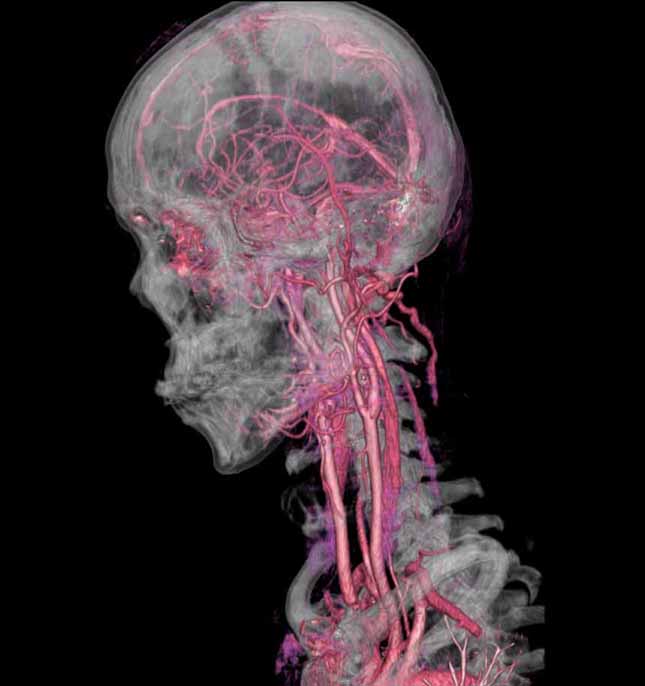

マルチスライスCT

下記など多くの診断ができます。

マルチスライスCT 診断画像

マルチスライスCT 診断画像

- 内頚動静脈・頭蓋内動静脈